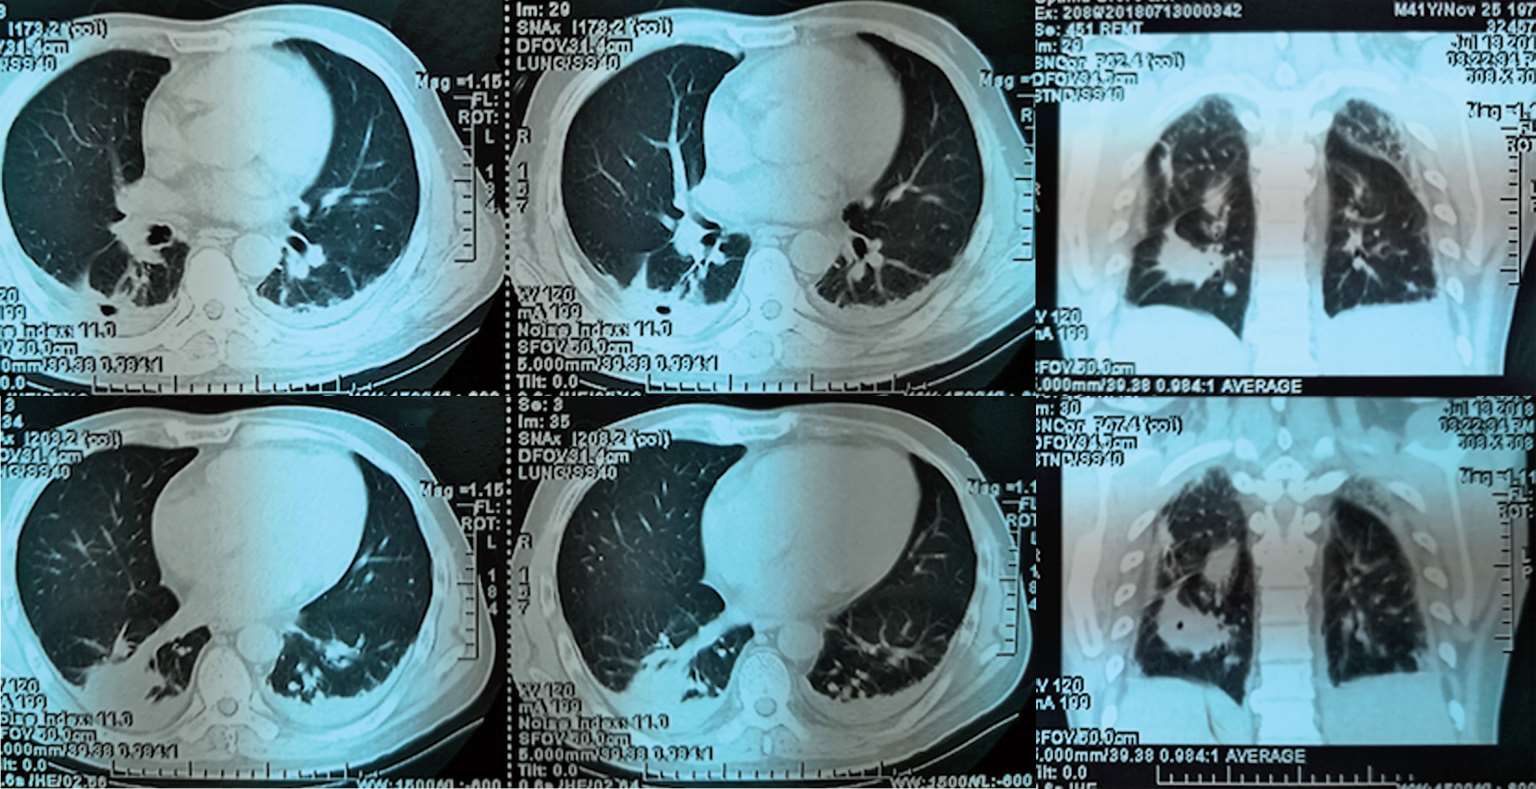

2018年7月12日晨家人发现患者倒地,当时呼之能应,精神萎靡,但四肢瘫软无力,胡言乱语,大小便失禁。至江苏省当地人民医院就诊,体温39.2℃,伴颈强直,脑膜刺激征阳性,肺部可闻及少许啰音。胸部CT(图2-1)示“右下肺见类圆形团块状稍高密度影,其内见气体影,右肺上叶近空洞样稍高密度影,周围见胸膜牵拉,胸膜不规则增厚。头颅CT示:脑内多发斑点状、小片状模糊密度影”。腹部CT(图2-2)示:肝脏、脾脏数枚小低密度影,肛周、脾周少许包裹性积液;左肾上极占位。给予布洛芬口服退热,但患者出现神志模糊,对答不切题,伴有可疑的癫痫发作,请神经内科会诊后考虑结核不能排除,遂转至南通市某医院呼吸科就诊。追问病史,患者起病前两周曾有上呼吸道感染病史,表现为少许咳嗽咳痰。

图2-1 2018年7月13日肺CT平扫:右下肺见类圆形团块状稍高密度影,其内见气体影,右肺上叶近空洞样稍高密度影,周围见胸膜牵拉,胸膜不规则增厚

7月30日患者行上腹部增强CT(图2-6),发现肝脾的低密度影已几近消失不见,但回报左肾占位性病变,考虑肿瘤可能。7月30日复查血T-SPOT. TB 仍为阴性。入院治疗两周后8月3日复查腰穿,压力220 mmH 2 O,脑脊液白细胞344×10 6 /L(↑),多核细胞32%,单核细胞68%,脑脊液糖2 mmol/L( ↓),同步血糖5.8 mmol/L,脑脊液蛋白质4 543 mg/L(↑),脑脊液氯106 mmol/L(↓)(表2-1)。脑脊液隐球菌荚膜抗原乳胶凝集试验及培养仍为阴性。此次脑脊液白细胞及蛋白质较前进一步升高,糖进一步下降。虽然此时患者体温已降至正常,但8月7日复查头颅增强MRI(图2-7)见颅内多发异常环形强化灶,部分病灶较前似有所增大,肺部CT平扫却见肺部病灶较前明显吸收减少。同时8月7日第二次脑脊液二代测序回报再次测得中间链球菌,序列数106。

图2-6 2018年7月30日上腹部增强CT

8月22日复查头颅及胸腰椎增强MRI示病灶均较前明显好转(图2-8)。患者已能对答切题及按照指令动作,GCS评分15分,拔除胃管后可自行进食。8月23日,调整方案为头孢曲松2 g ivgtt q12h联合青霉素640万U ivgtt q8h继续抗链球菌治疗。9月30日复查腰穿,脑脊液较前进一步好转(表2-1)。10月9日复查头颅、胸腰椎增强MRI及肺CT,病灶均进一步缩小(图2-9)。

图2-9 2018年10月9日头颅、胸腰椎增强MRI、肺平扫CT